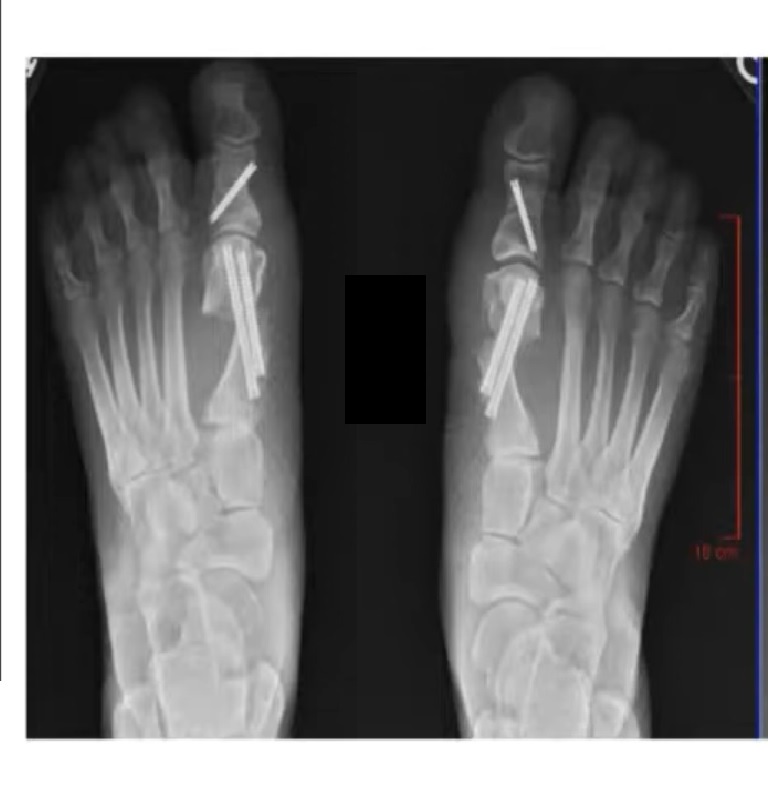

Photo Gallery Bunion Doctors Virginia Beach Orthopaedic Surgeons

MIS Bunion Correction — Orthopedic Bunion Surgeon Dr tan ken jin is a fellowship. Treatment treatment what is bunion surgery? Mbbs (singapore) mrcs (edin) mmed (ortho) frcs. Meet dr tan ken jin (bunion surgery specialist) dr tan ken jin is a fellowship trained orthopaedic surgeon with a subspecialty interest in foot and. Find out the causes and treatment options for bunion, and if there is a need. Orthopedic Bunion Surgeon.